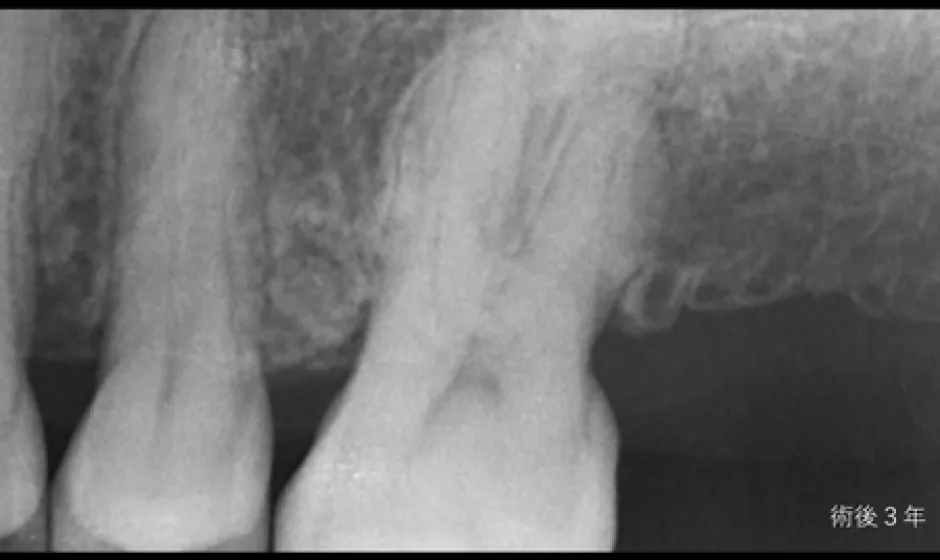

02歯周病・

重度歯周病治療歯周病は痛みが少ないまま進行し、気づいた時には歯がグラつく、膿が出る、噛みにくいといった状態になりやすい病気です。けれど、重度でも「もう無理」と決めつける前に、歯ぐき・骨・噛み合わせの状態を丁寧に評価し、今できることを一つずつ積み上げれば、守れる歯はあります。

当院では検査に基づき、基本治療から必要に応じた外科的治療や再生療法の検討まで、長期維持を見据えて段階的に進めます。津市で歯周病を本気で治したい方に、寄り添える歯科医院でありたいと考えています。症例1

- 治療名

- 【重度歯周病】歯周組織再生療法による機能回復

- 患者様

- 40代女性

- 執刀医

- Dr. 大杉

- 治療期間

- 約1年(初期治療・経過観察期間含む)

- 治療費

- 250,000円(税込)

- リスク

- 術後に一時的な腫れや痛みが生じることがあります(鎮痛剤等の処方で管理を行います)。

また、喫煙等の生活習慣によっては治癒不全のリスクが高まる場合があります。